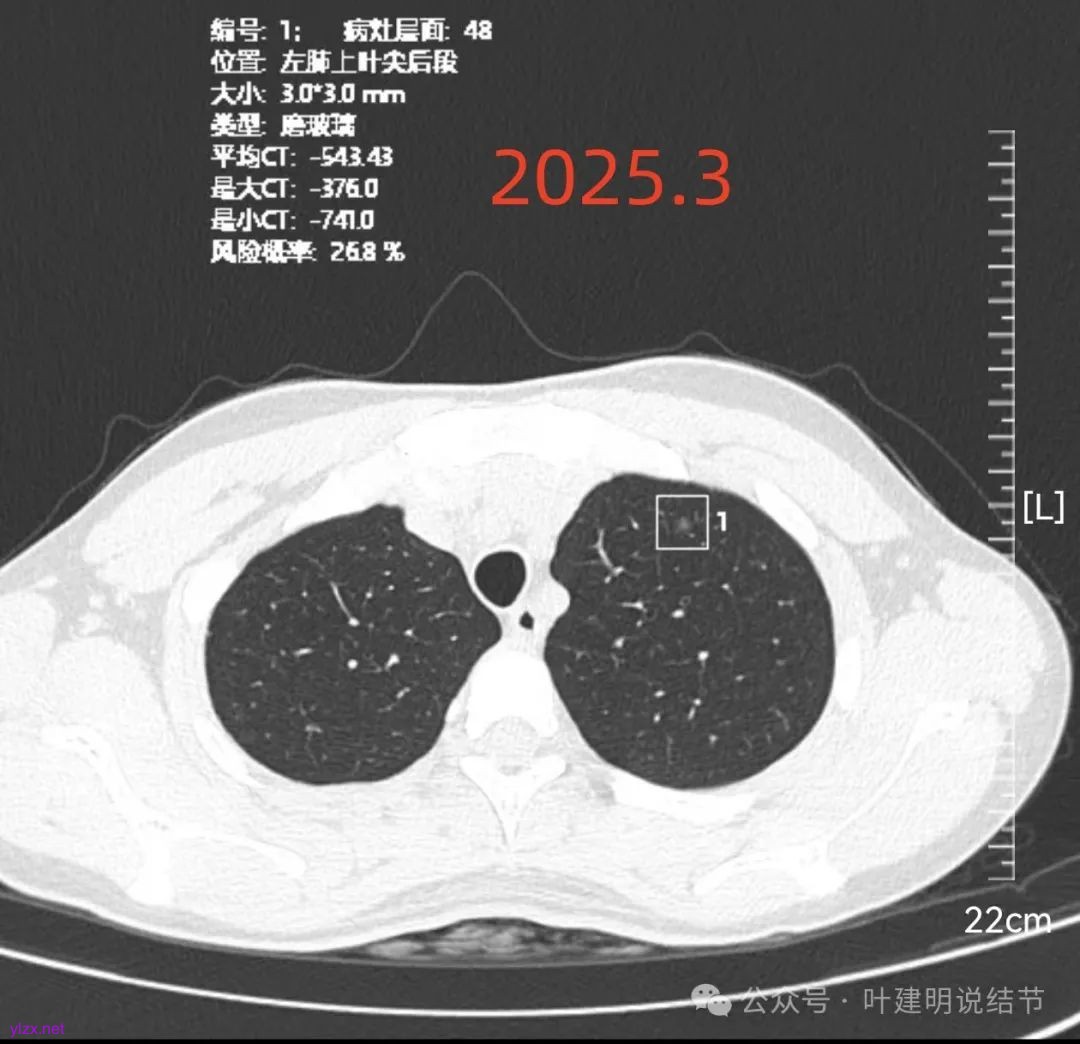

再看2025年3月的影像:

各病灶均无明显吸收好转,但显然也说不上有明显进展。所以基本上要考虑是肿瘤范畴的(包括肺泡上皮不典型增生或肺泡上皮增生)。但危险性显然不算高,至少近2年了没有什么进展,即使病灶6最厉害的也是纯磨密度伴空腔。

再来看风险最大的病灶6的连续层面:

血管从旁过,没有受结节影响。